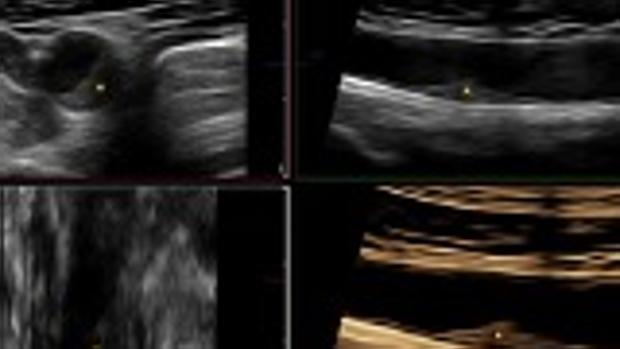

Casi la mitad de las personas aparentemente sanas de entre 40 y 50 años podría estar desarrollando una acumulación de placas de grasa –ateroma- en las arterias y de una forma mucho más rápida de lo que se pensaba hasta ahora. La revista The Journal of American College of Cardiology (JACC) publica hoy nuevos datos del estudio PESA-CNIC-Santander que demuestran que las placas de ateroma se extienden rápidamente por las arterias de sujetos asintomáticos en el 40% de las personas entre 40 y 50 años. Los investigadores del Centro Nacional de Investigaciones Cardiovasculares (CNIC), dirigidos por Valentín Fuster, Director del CNIC, han visto, además, que la progresión de la aterosclerosis está directamente relacionada con los factores tradicionales de la enfermedad cardiovascular: edad, sexo, hipertensión, colesterol, tabaco y diabetes. El PESA-CNIC-Santander (Progresión de la aterosclerosis subclínica temprana), estudio realizado en colaboración entre el CNIC y el Banco de Santander, incluye a 4.200 hombres y mujeres sanos de mediana edad que se están siguiendo mediante tecnología de imagen y biomarcadores sanguíneos de ómicas desde hace más de 10 años. El uso de técnicas de imagen no invasivas, asegura el Dr. Fuster, «nos permite identificar la progresión y detectar el avance de la enfermedad de forma más precoz que con otros marcadores clásicos, como la presencia de calcio coronario mediante TAC, permitiendo así adelantar la identificación de aquellos individuos con mayor riesgo y que se podrían beneficiar de intervenciones tempranas». Gracias a estas técnicas de imagen, especialmente las más sencillas, accesibles y que no necesitan radiación, como la ecografía vascular 2D y 3D,explica Borja Ibáñez, director de Investigación Clínica del CNIC, «podemos detectar y cuantificar la carga o el volumen de enfermedad aterosclerótica y monitorizarla de una forma precisa para así identificar a aquellos individuos que se puedan beneficiar potencialmente de una prevención más intensiva de forma precoz». Un estudio del CNIC publicado en JACC demuestra que las placas de ateroma se extienden rápidamente por las arterias de sujetos asintomáticos en el 40% de las personas entre 40 y 50 años analizadas en el estudio PESA-CNIC-Santander. Lo que ahora aporta el estudio es un seguimiento a 3 años del estudio PESA en el que se ha llevado a cabo la primera comparación directa entre ambos marcadores de riesgo en imagen, el calcio coronario por TAC y la carga de aterosclerosis carotidea y femoral por ecografía 2D/3D. Y los resultados, destaca Beatriz López-Melgar, autora principal del artículo, «muestran que la ecografía de las arterias periféricas es capaz de detectar la progresión de la aterosclerosis de una forma más eficiente que el estudio del calcio coronario por TAC». Lo más habitual es que la enfermedad aterosclerótica -caracterizada por el depósito de sustancias lipídicas en las paredes de las arterias- se detecte en estadios avanzados, cuando ya ha provocado eventos clínicos como infarto de miocardio, accidente cerebrovascular u otros. El tratamiento de este tipo de patologías, cuando ya ha dado síntomas, resulta limitado ya que en un elevado porcentaje los individuos afectados ven disminuida su calidad de vida y, por otro lado, supone un elevado coste económico para el del sistema sanitario. «Hasta este estudio, el primero que analiza la progresión de la aterosclerosis con intervalos frecuentes, se pensaba que esta enfermedad progresaba muy lentamente a lo largo de la vida. Sin embargo, en contra de esta idea, dicha progresión es muy rápida en un 40% de los casos analizados», asegura Ibáñez. En el futuro, añade, «podremos saber con los datos del estudio PESA si esta progresión tiene que ver con el desarrollo futuro de eventos cardiovasculares. Hasta ahora, la velocidad de progresión no había sido considerada a la hora de categorizar el riesgo de los individuos». Un estudio del CNIC publicado en JACC demuestra que las placas de ateroma se extienden rápidamente por las arterias de sujetos asintomáticos en el 40% de las personas entre 40 y 50 años analizadas en el estudio PESA-CNIC-Santander. Los investigadores del CNIC ya habían observado, en análisis previos del PESA, que la presencia de aterosclerosis es frecuente en individuos jóvenes y de mediana edad. «Con este estudio –asegura el Dr. Fuster- hemos determinado cómo progresa la aterosclerosis en sus etapas más iniciales, sin la presencia de síntomas». Los investigadores concluyen que, estos hallazgos, aunque deben ser validados en un futuro próximo con la presencia de eventos en la cohorte del PESA, son de gran valor para identificar estrategias que permitan prevenir la epidemia de la enfermedad cardiovascular.Fuente Salud https://ift.tt/3dZeRpw